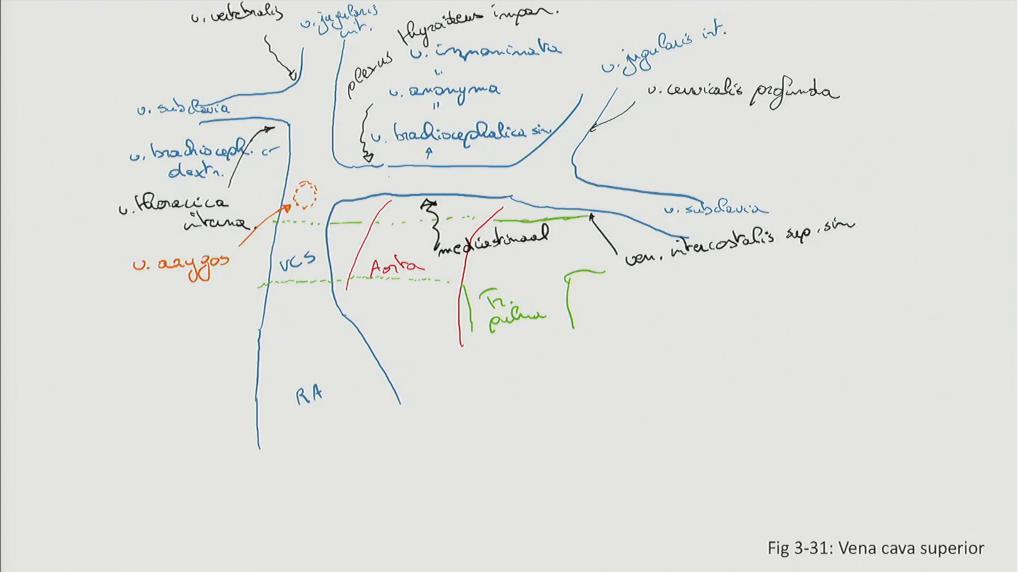

Fig 3.31: v. cava superior

distaal (vanaf elleboog, knie): diepe venen ontdubbeld aorta truncus pulmonalis -

atrium dextrum (RA)

-

v cava superior (VCS)

-

v brachiocephalica dextra (korter dan sinistra)

-

v brachiocephalica sinistra = v. anonyma = v. innominata

v azygos (oranje, posterior)

-

kleinere takken (minder klinisch belang, veel variatie)

mediastinale takken v intercostalis superior sinistra plexus (venosus) thyroideus impar v vertebralis dextra (vaak geen sinistra) v thoracica interna v cervicalis profunda

|

Sobotta: Fig 5.18